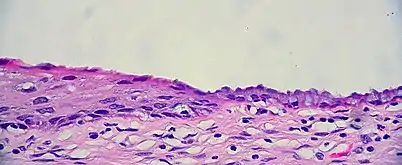

The squamocolumnar junction of the cervix: The ectocervix, with its stratified squamous epithelium, is visible on the left. Simple mucinous columnar epithelium, typical of the endocervix, is visible on the right. A layer of connective tissue is visible under both types of epithelium.

The cervical canal is generally lined by "endocervical mucosa" which consists of a single layer of mucinous columnar epithelium. However, after menopause, the functional squamocolumnar junction moves into the cervical canal, and hence the distal part of the cervical canal may be lined by stratified squamous epithelium (conforming to a "type 3 transformation zone").[2]